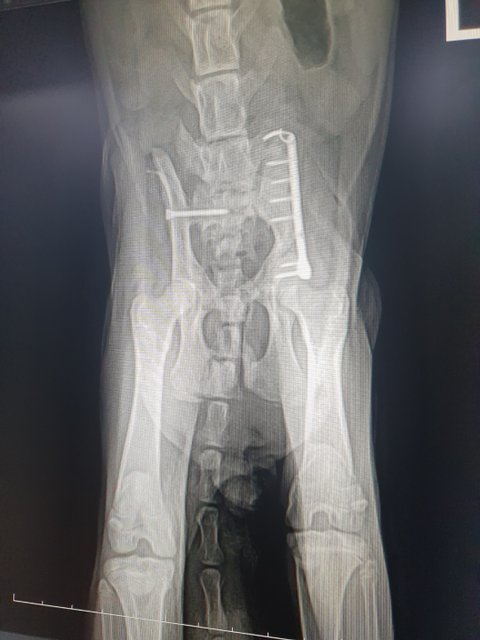

병원에 가서 진찰을 해보니 교통사고가 났던 것 같다 꼬리는 괴사해서 잘라야하고  엑스레이를 찍어보니 골반도 다쳐서 수술하지 않으면 나중엔 배변이 어렵고 CT기계가 없어 찍진 못했지만, 골반쪽이 다쳤기 때문에 신경에도 이상이 있을 것 같다 왼쪽다리도 다쳤는데 고양이가 아직 다 성장하지 못해 성장불균형이 생겨서 절뚝거리게 될 것이라 했고 수술을 하려면 엑스레이 상으로는 대략적으로 150만원정도 나올 것이라고 하였습니다.(원래 더 많이 나오는데 길고양이라서 입원비도 빼주셨습니다)

골반 왼쪽 부러짐, 오른쪽 탈골 수술을 진행하였고.

골반 수술 검사비 제외 150만원 비용 발생했습니다.